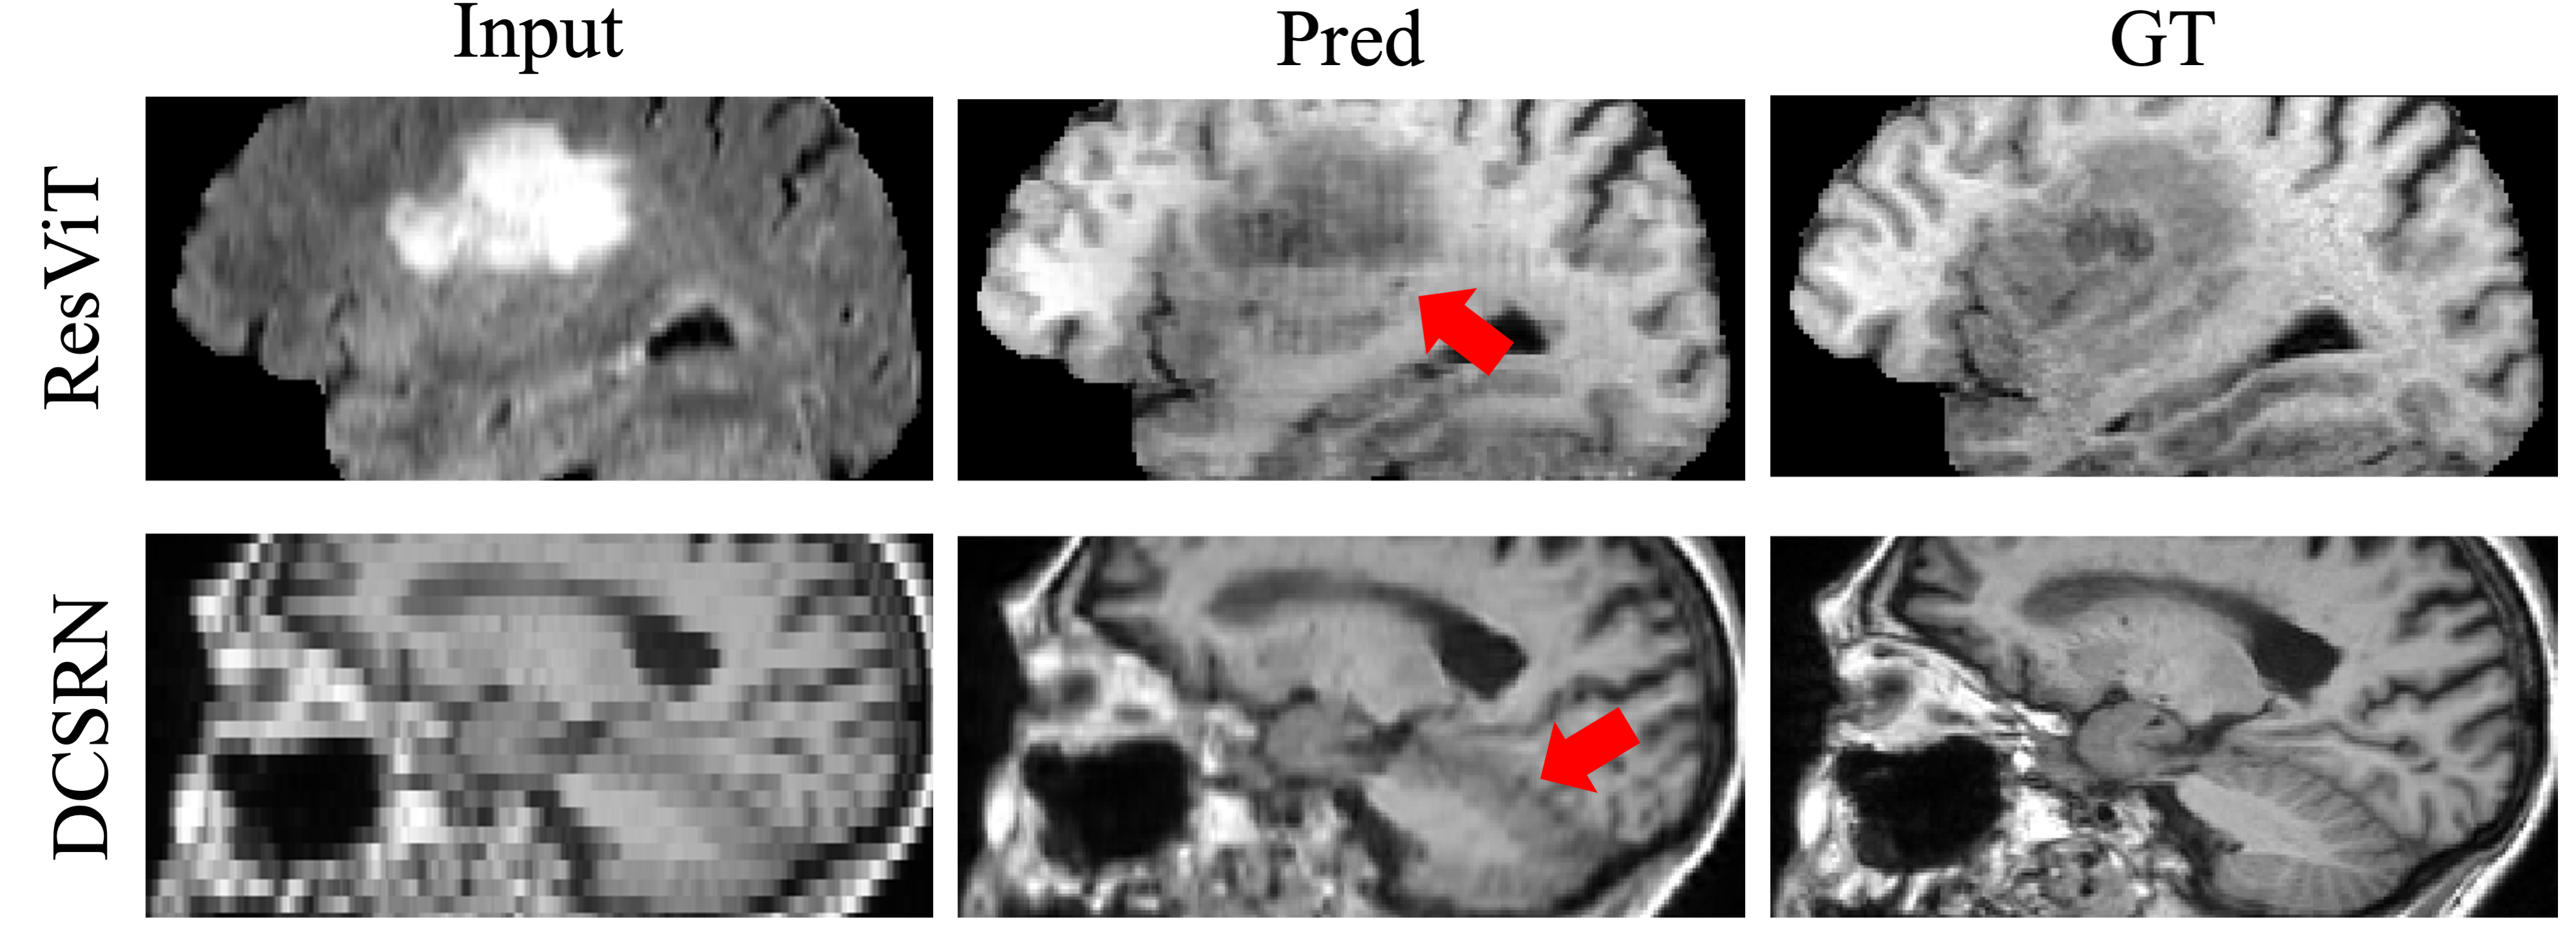

Another limitation of these deep learning-based methods is the inadequate treatment of alias frequencies. Aliasing is a prevalent phenomenon in the MRI reconstruction field, especially in 2D MRI acquisitions with low resolution in the through-plane direction, where aliasing artifacts may arise due to Nyquist criteria [21]. Additionally, aliasing effects should be carefully considered when reconstructing from undersampled k-space data [22]. However, current works for MRI synthesis often overlook the impact of aliasing, despite treating the signals within the neural network as discrete entities. Consequently, these works produce unnatural details, and even aliasing artifacts as shown in Fig. 2.

Refer to caption

Figure 2: The synthetic results produced by the previous CMS (ResViT) and SR (DCSRN) methods. All of the generated MR images suffer from artifacts, as compared with the reference ground truth.